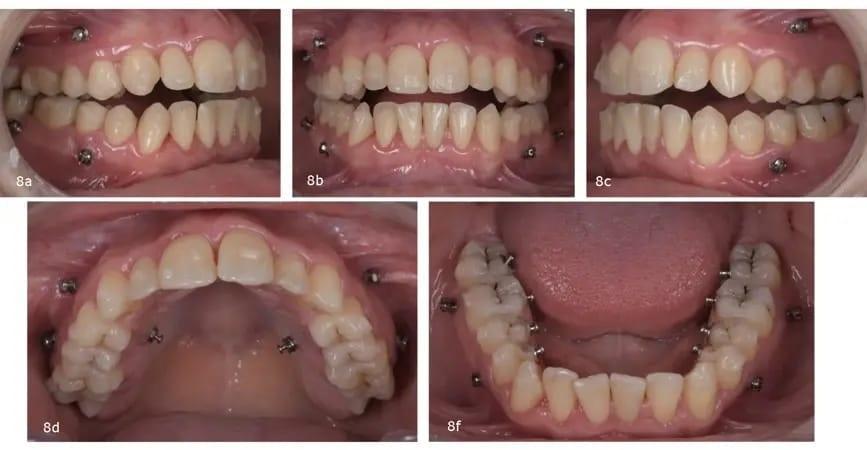

При первом приеме были прикреплены аттачменты. С буккальной стороны верхней челюсти были установлены мини-винты (1,6 × 10,0 мм) между первым и вторым премолярами и между первым и вторым молярами и с небной стороны - между первым и вторым премолярами. Пациентке было рекомендовано поверх элайнеров носить вертикальные эластики диаметром 12,7 мм, проходящие с двух сторон от буккальных до небных мини-винтов. В нижнюю челюсть с буккальной стороны были также поставлены мини-винты между первым и вторым премолярами и между первым и вторым молярами. Пациентку проинструктировали надевать эластики от этих мини-винтов поверх элайнеров на лингвальные кнопки (фото 8).

Фото 8a–e: Ситуация после установки верхнечелюстных и нижнечелюстных аттачментов и мини-винтов.